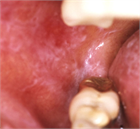

1. 口腔の粘膜疾患は口腔粘膜に症状を呈する病変の総称であり、その中にはさまざまな病変が含まれる。口腔粘膜に限局した疾患、顎顔面領域における病変が波及して口腔粘膜症状を呈したり、自己免疫疾患、内科疾患、皮膚疾患の部分症状が口腔粘膜に出現することもある。口腔粘膜に発現した疾患の鑑別診断により、全身性疾患が発見されることを加筆した。

1. 口腔の粘膜疾患は口腔粘膜に症状を呈する病変の総称である。

1. 口腔の粘膜疾患は口腔粘膜に限局して発現する病変のほかに、内科疾患、自己免疫疾患、皮膚疾患などの部分症状として口腔粘膜に病変が出現するものがある。